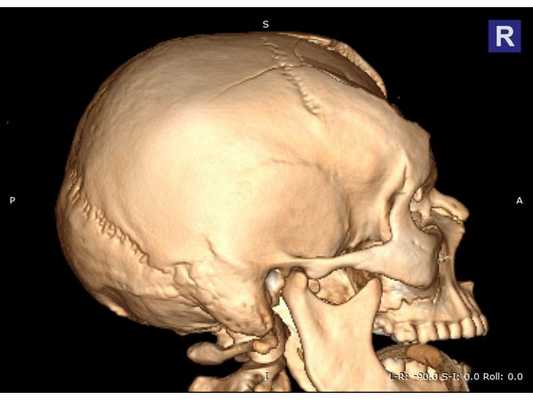

КТ головного мозга: оскольчатый вдавленный перелом лобной кости, линейный перелом ската затылочной кости, а также перелом лицевого отдела черепа III степени по Le Fort с остаточной деформацией стенок; множественные ушибы и отёк вещества головного мозга лобных долей; скопление крови в пазухах носа. КТ шейного и поясничного отделов позвоночника: травм и патологий нет. КТ грудной клетки и грудного отдела позвоночника: ушиб правого лёгкого. Офтальмологический осмотр: контузия правого глазного яблока тяжёлой степени, скопление крови между сетчаткой и пигментным эпителием левого глаза.

Сочетанная черепно-челюстно-лицевая травма. Открытая проникающая черепно-мозговая травма. Ушиб головного мозга тяжёлой степени с преимущественным поражением лобных долей и формированием очагов размозжения в полюсно-базальных отделах. Многооскольчатый вдавленный перелом лобной кости, переходящий на основание черепа. Перелом лицевого отдела черепа III степени по Le Fort с деформацией стенок правой глазницы. Ушиб правого глаза тяжёлой степени, субретинальное кровоизлияние левого глаза.